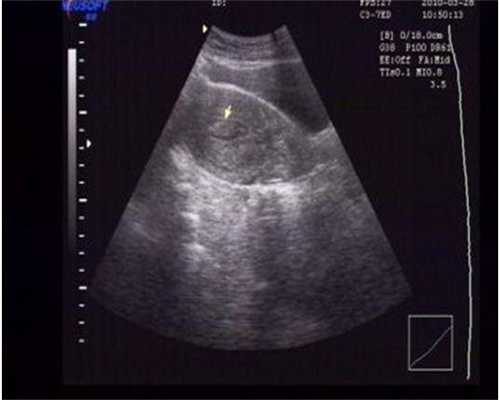

而育龄女性子宫内膜在月经周期中会有很大的变化,一般在5-15mm之间。

在一个月经周期中,月经结束后,卵泡开始发育,卵泡分泌雌激素,雌激素刺激子宫内膜的基底层,子宫内膜就会慢慢的生长。到了月经中期卵泡成熟,排卵。排卵后雌激素水平有个短暂的下降。这个时候子宫内膜大约有8mm,这个时期的子宫内膜叫做增生期的子宫内膜。但很快卵泡排出后卵巢上形成黄体,黄体能分泌雌激素和孕激素。雌激素使子宫内膜继续增厚同时由于孕激素的作用,子宫内膜的血管增生,子宫内膜的腺体中也富含糖原,子宫内膜营养非常的丰富。这个时期的子宫内膜叫做分娩期的子宫内膜。虽然子宫内膜也在长厚,但孕激素抑制子宫内膜腺体的无序增生。到月经前,子宫内膜厚度约达到12-15mm左右。大约排卵后2周,如果没有受孕。卵巢上的黄体萎缩,不再分泌雌激素和孕激素,雌激素孕激素水平骤然下降,子宫内膜中血管断裂、子宫内膜脱落,月经来潮。

这些子宫内膜的过度增生首先是表现的子宫内膜增厚。但最根本的是病理的变化,而不是厚度的变化。